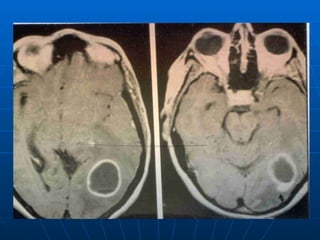

Infecciones Supuradas del SNC Absceso cerebral Son poco frecuentes, asociados a infección contigua, trauma o diseminación hematógena, los criptogénicos  son raros etapas: cerebritis precoz y tardía, absceso encapsulado precoz y tardío. Las dos primeras etapas son de tratamiento médico posible. síntomas: cefalea, fiebre, cambio del sensorio, foco, nauseas y vómitos, convulsiones diagnóstico: imágenes, no hacer PL. TAC con contraste ev.y RMN. tratamiento médico: lesiones < 3 cm, o múltiples, o asociadas a meningitis, o con mejoría clínica y reducción precoz con atb tratamiento quirúrgico: deterioro neurológico, aumento de tamaño en TAC, estables luego de 6 semanas de tratamiento

Infecciones Supuradas delSNC Absceso cerebral Son poco frecuentes, asociados a infección contigua, trauma o diseminación hematógena, los criptogénicos son raros etapas: cerebritis precoz y tardía, absceso encapsulado precoz y tardío. Las dos primeras etapas son de tratamiento médico posible. síntomas: cefalea, fiebre, cambio del sensorio, foco, nauseas y vómitos, convulsiones diagnóstico: imágenes, no hacer PL. TAC con contraste ev.y RMN. tratamiento médico: lesiones < 3 cm, o múltiples, o asociadas a meningitis, o con mejoría clínica y reducción precoz con atb tratamiento quirúrgico: deterioro neurológico, aumento de tamaño en TAC, estables luego de 6 semanas de tratamiento